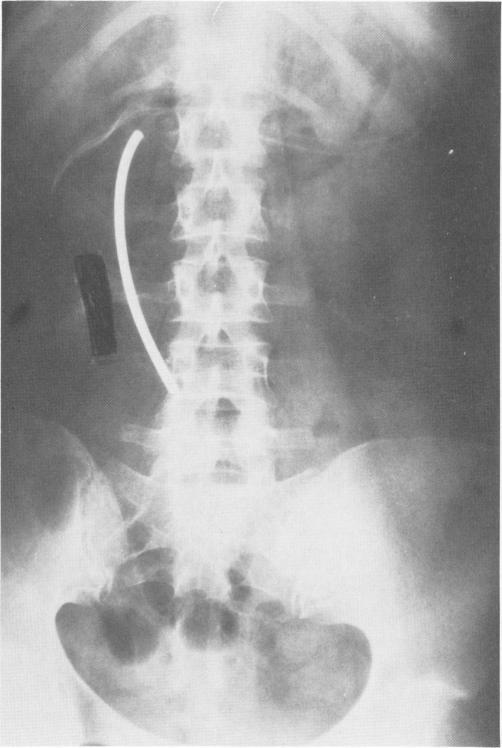

A naso-gastric duodenal mercury tip weighted sump tube has been developed that will efficaciously decompress small bowel in cases of paralytic ileus, partial or complete mechanical obstruction, and can easily be introduced into the duodenum by a nurse, house staff or attending physician. The tube also may be used for diagnostic purposes to obtain gastrointestinal, pancreatic or biliary secretions.

已研发出一种鼻胃十二指肠汞头加重引流管,在麻痹性肠梗阻、部分或完全机械性梗阻病例中,它能有效地对小肠进行减压,护士、住院医生或主治医生可轻松将其插入十二指肠。该引流管也可用于诊断目的,以获取胃肠道、胰腺或胆汁分泌物。